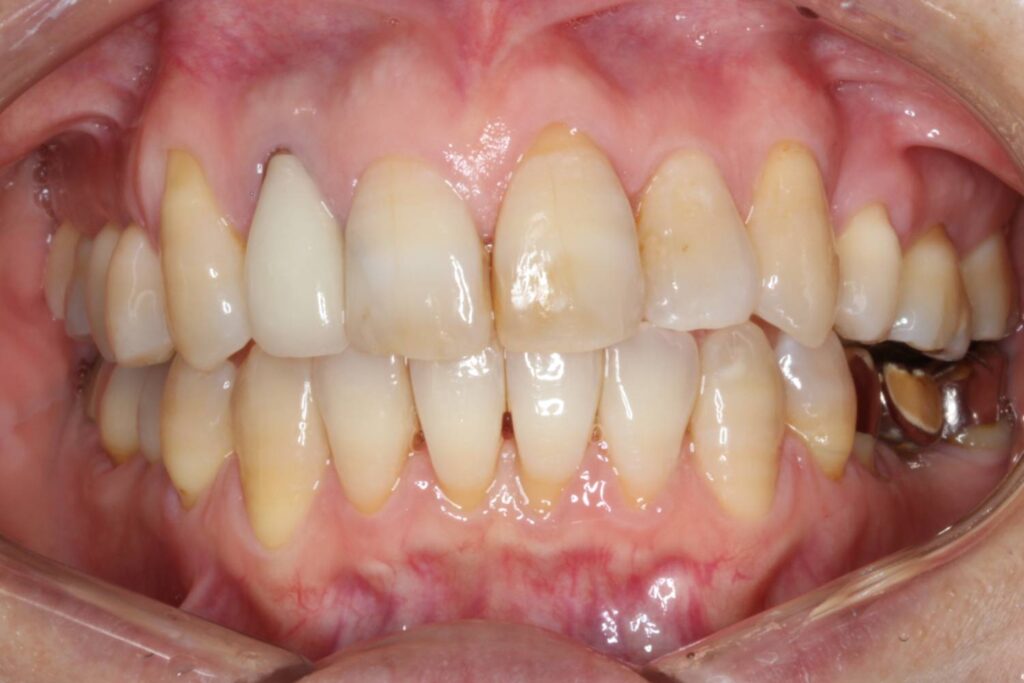

治療後は、上下顎の中心が一致し、でこぼこが解消されて前歯の印象が良くなりました。

また、ブリッジの部分も無事に壊さずに、上顎の歯と問題なく噛み合っています。

After